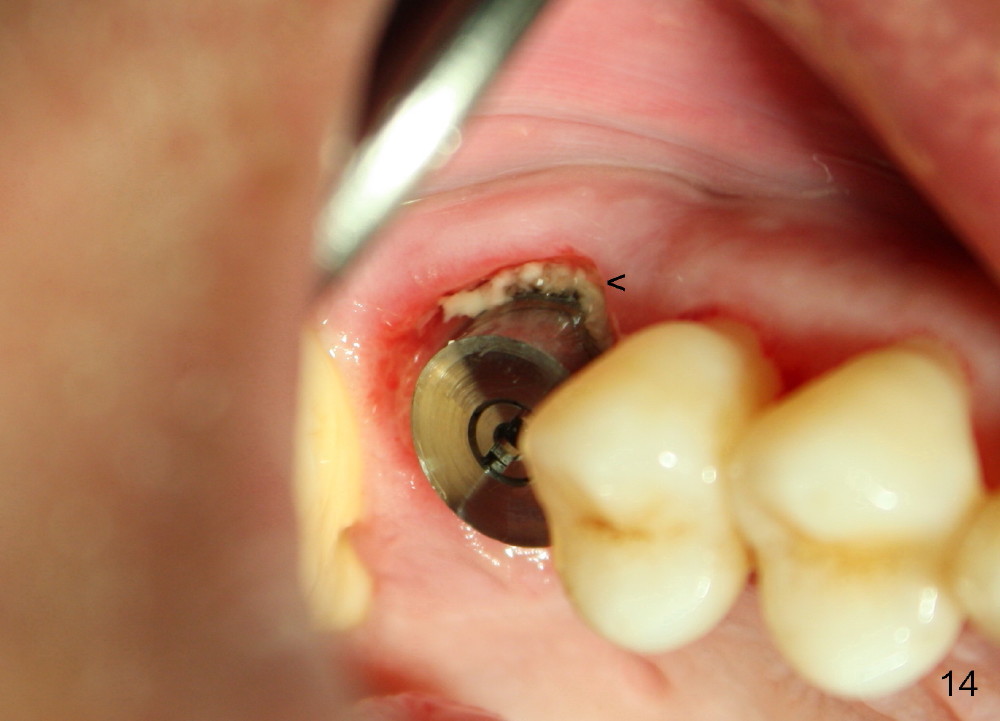

The upper right 1st molar of a 48-year-old man has severe perio endo disease (Fig.1 #3); the bone height for immediate implant (Fig.2) is about 3.5 mm (Fig.1 vertical line). There is a buccal (Fig.3 B) abscess (*); the palatal (Fig.4 P) root is exposed. After extraction, the socket available for immediate implant (Fig.5,6 S) is buccal (without septum), whereas the apex of the palatal root is far away from the main socket. In fact there is an advantage: the socket is smaller. Osteotomy is created in the main socket as palatal as possible, using osteotomes, reamers and taps (Fig.7 T). The sinus floor is lifted (Fig.7 ^). When 7x17 mm implant is placed (Fig.8 I), the insertion torque is >60 Ncm. The remaining socket (Fig.8 *) is to be packed with mixture of autogenous bone, allograft and synthetic bone (Osteogen) (Fig.9,10 <). Immediate insertion of an abutment (Fig.8-10 A) helps retain perio dressing (Fig.11,12). No collagen membrane is used in this case to cover the bone graft before placement of perio dressing. Postop the patient cannot tolerate oral Amoxicillin because of stomach upset. The dose is reduced. Two weeks postop, the perio dressing is stable, but discolors (Fig.13). When the dressing is removed, the buccal bone graft is exposed, which is not abnormal. What is unusual is discoloration (Fig.14). The significance of the latter is not revealed until 3 months postop when the patient remains asymptomatic, but there is an apical fistula (Fig.15 <). There is a communication between the fistula and the buccal sulcus of the implant: water passing freely. Based on the position of the buccal plate of the neighboring teeth (*), the buccal plate of the implant should be lost, which is consistent with finding of PA (Fig.16, as compared to Fig.8). Guided bone regeneration seems necessary.